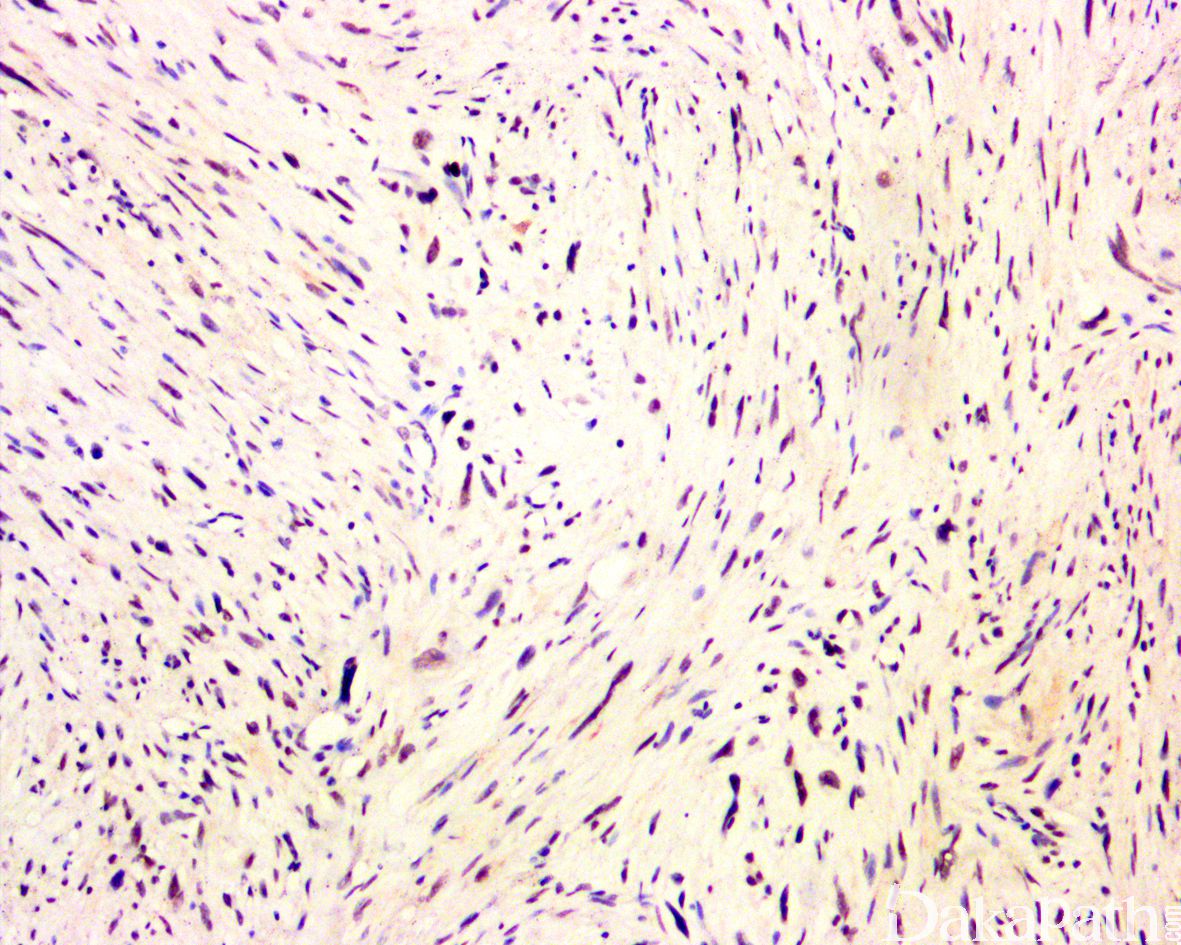

免疫组织化学染色:

均弥漫强表达 CD34,约 60%局灶表达广谱细胞角蛋白,其他标志物包括 EMA、P53. 血管内皮标志物、肌源性标志物、黑色素标志物、树突状细胞和组织细胞标志物以及白细胞共同抗原等均阴性;INI-1 免疫标记显示肿瘤无表达缺失;Ki67 增殖指数低,通常<1%。